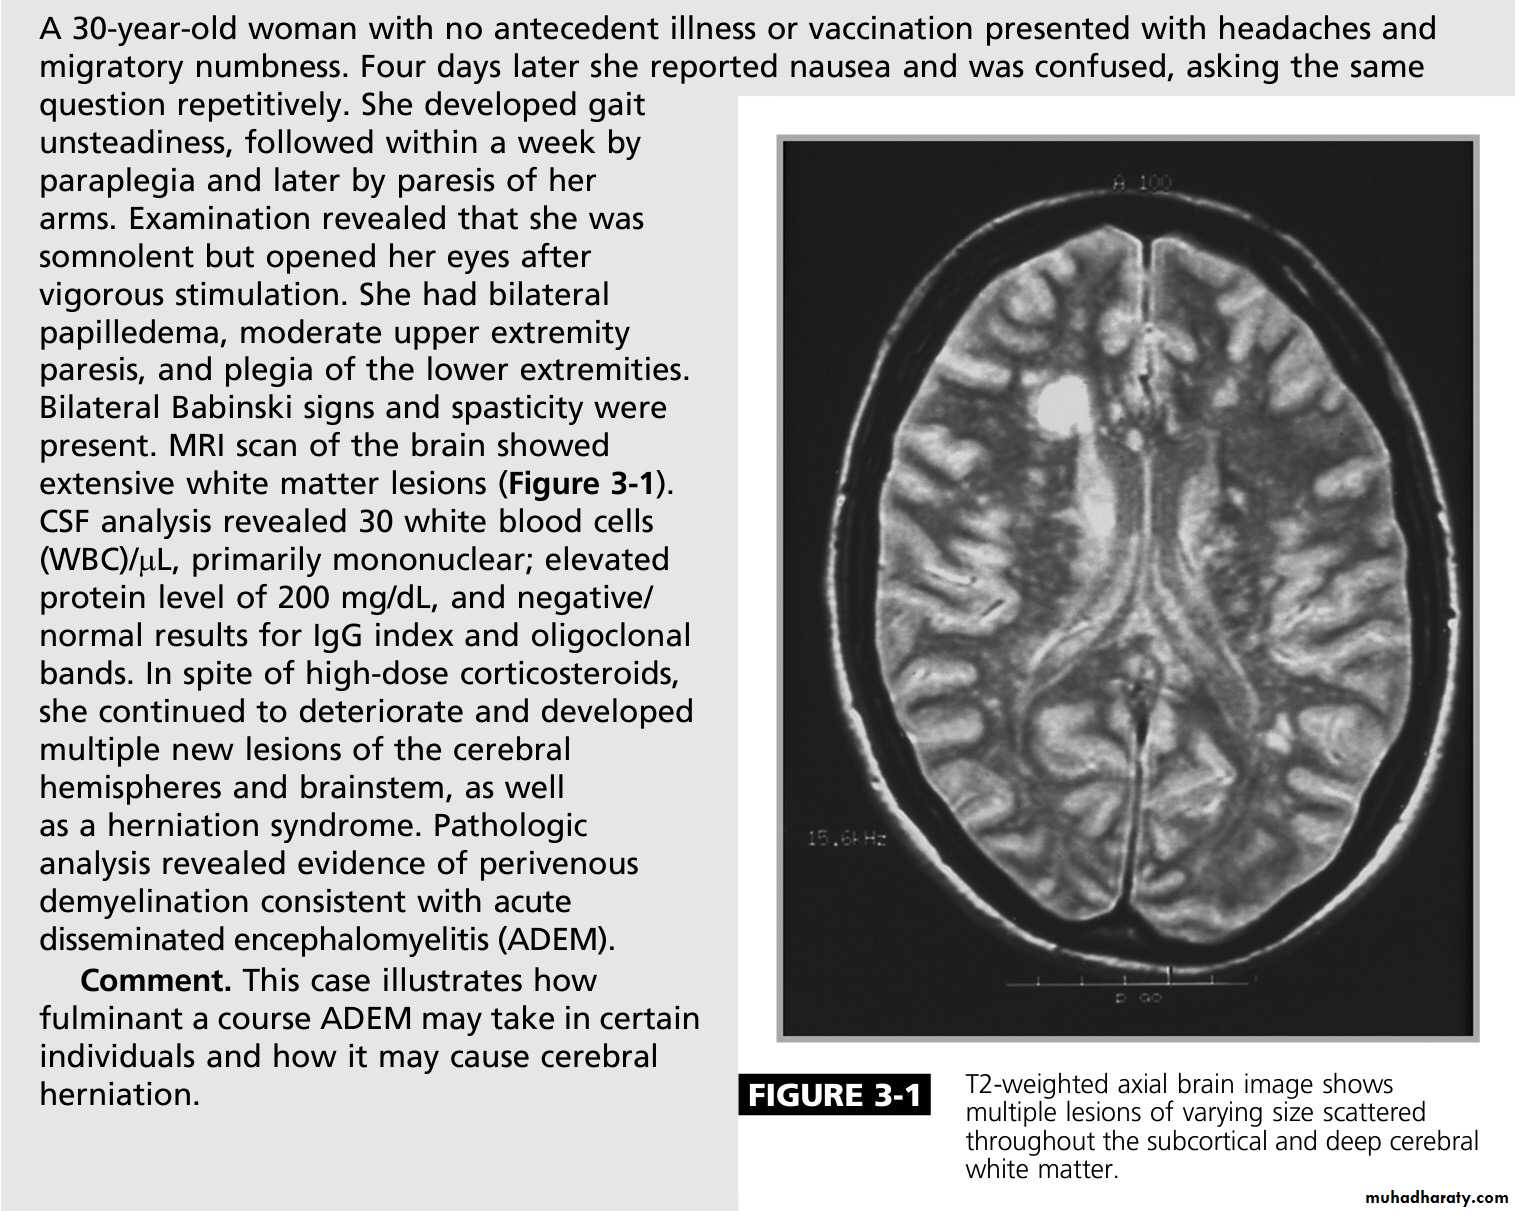

Acute disseminated encephalomyelitis

This is an acute monophasic demyelinating condition in which there are areas of perivenous demyelination widely disseminated throughout the brain and spinal cord. The illness may apparently arise spontaneously but often occurs a week or so after a viral infection, especially measles and chickenpox, or following vaccination, suggesting that it is immunologically mediated.

Clinical features:

Headache, vomiting, pyrexia, confusion and meningism may be presenting features, often with focal or multi focal brain and spinal cord signs. Seizures or coma may occur.

MRI shows multiple high-signal areas in a pattern similar to that of MS, although often with large confluent areas of abnormality. The CSF may be normal or show an increase in protein and lymphocytes (usually 200 cells/L) . The clinical picture may be very similar to a first relapse of MS.

Management:

The disease may be fatal in the acute stages but is other wise self-limiting. Treatment with high-dose intra venous methylprednisolone, using the same regimen as for a relapse of MS, is recommended.